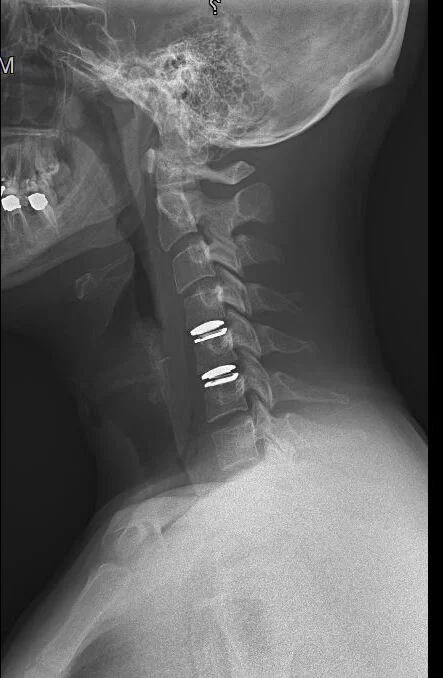

Η επέμβαση γίνεται υπό γενική αναισθησία και συχνά υπό νευροπαρακολούθηση. Ο νευροχειρουργός πραγματοποιεί μια μικρή τομή στην πρόσθια επιφάνεια του αυχένα, περίπου στο ύψος του μεσοσπονδύλιου διαστήματος που πάσχει και πρέπει να χειρουργηθεί. Με τη βοήθεια μικροσκοπίου αφαιρείται ο κατεστραμένος δίσκος και τα οστεόφυτα. Αυτό γίνεται με μικρές φρέζες ή εργαλεία που λέγονται οστεοτόμοι. Αφού τα νεύρα και ο νωτιαίος μυελός έχουν αποσυμπιεστεί πλήρως, τότε τοποθετείται ένα μόσχευμα στο διάστημα (Μοσχεύματα. Οι λεγόμενοι κλωβοί ή cages: Εικόνα 3). Σε μερικές περιπτώσεις, αν υπάρχει ένδειξη, μπορεί να τοποθετηθεί ένας τεχνητός δίσκος (Εικόνα 2). Η τοποθέτηση ελέγχεται κατά τη διάρκεια του χειρουργείου με ακτινοσκοπικό έλεγχο. Αφού τοποθετηθούν τα μοσχεύματα, η τομή κλείνεται.